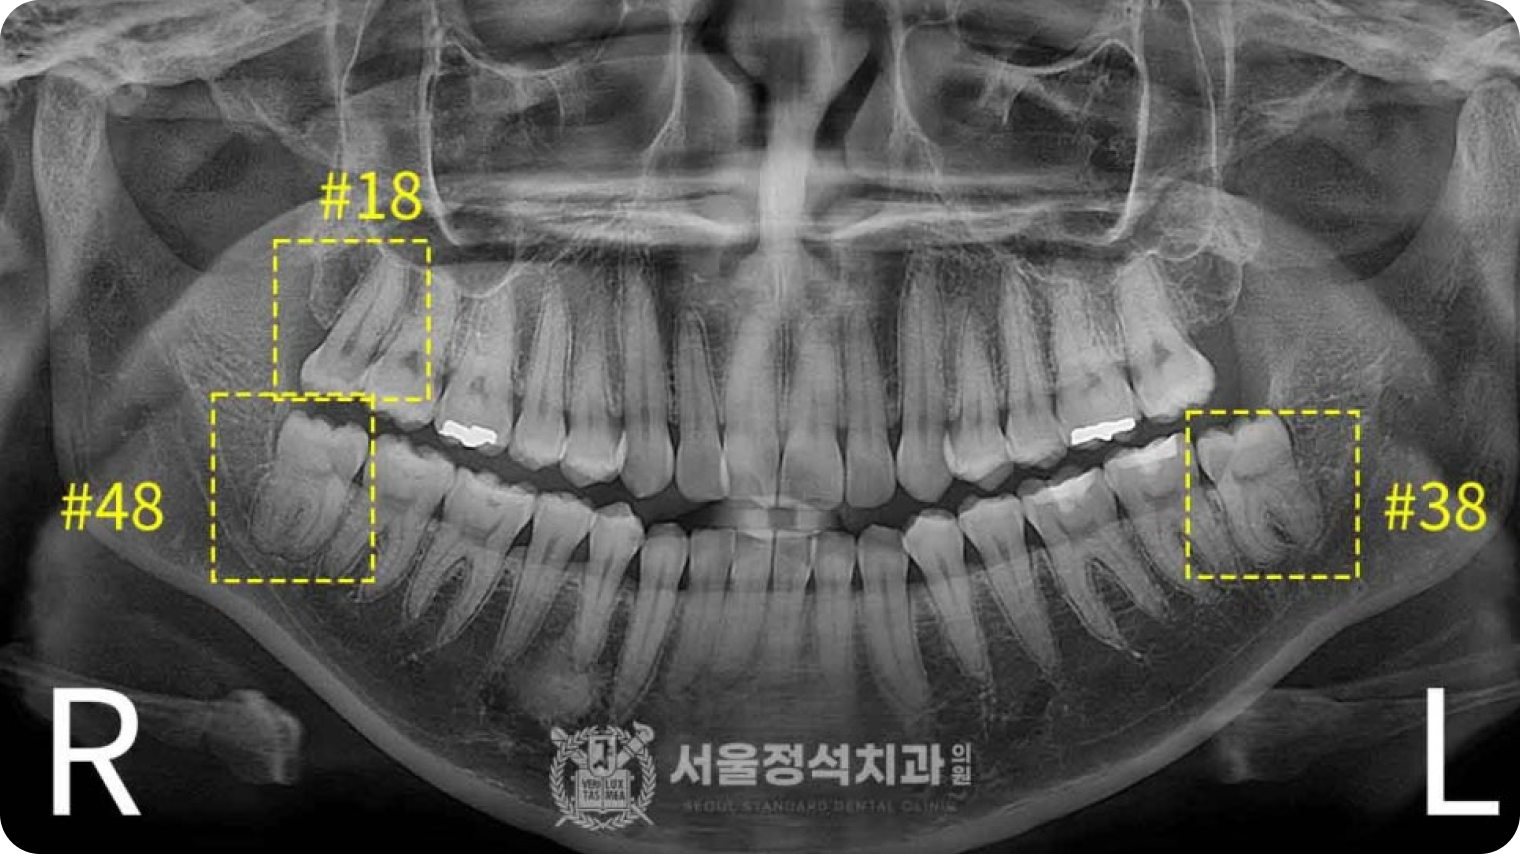

당일 사랑니 발치

당일 사랑니 발치

당일 사랑니 발치

사랑니는 영구치열을 방해하고 관리가 어려워 충치, 염증 등 문제를 일으킵니다. 신경까지 고려하는 당일 사랑니 발치로 빠르고 안전하게 해결합니다.